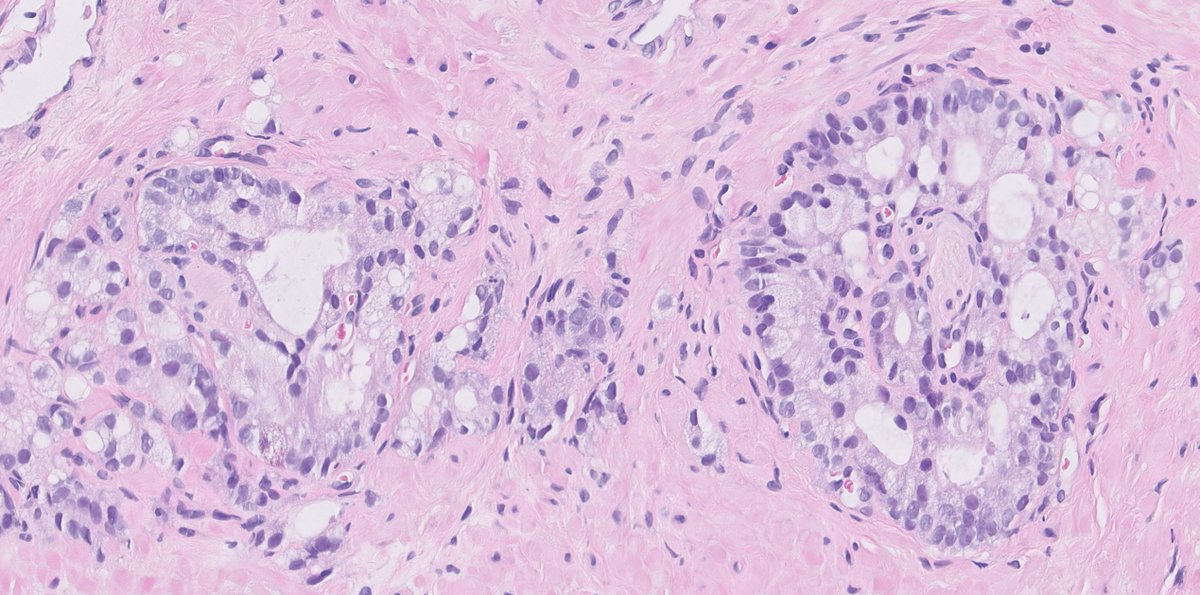

@kis_lorand

#yourdailyGleasongrading is back with a quizz 😁... Guess how was this tiny cancerfocus measuring 1 mm graded? I hope it is visible that the glands are perineural...The last picture is p63 (brown)-AMACR (red) IHC 👇👇 #GUpath #pathology